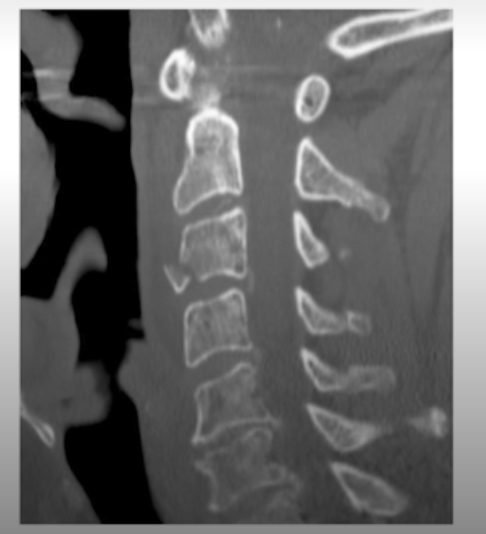

What is the fracture seen in the image below and how is it caused?

Flexion teardrop fracture of the vertebral body - results from extreme flexion. Often associated with ligamentous damage.